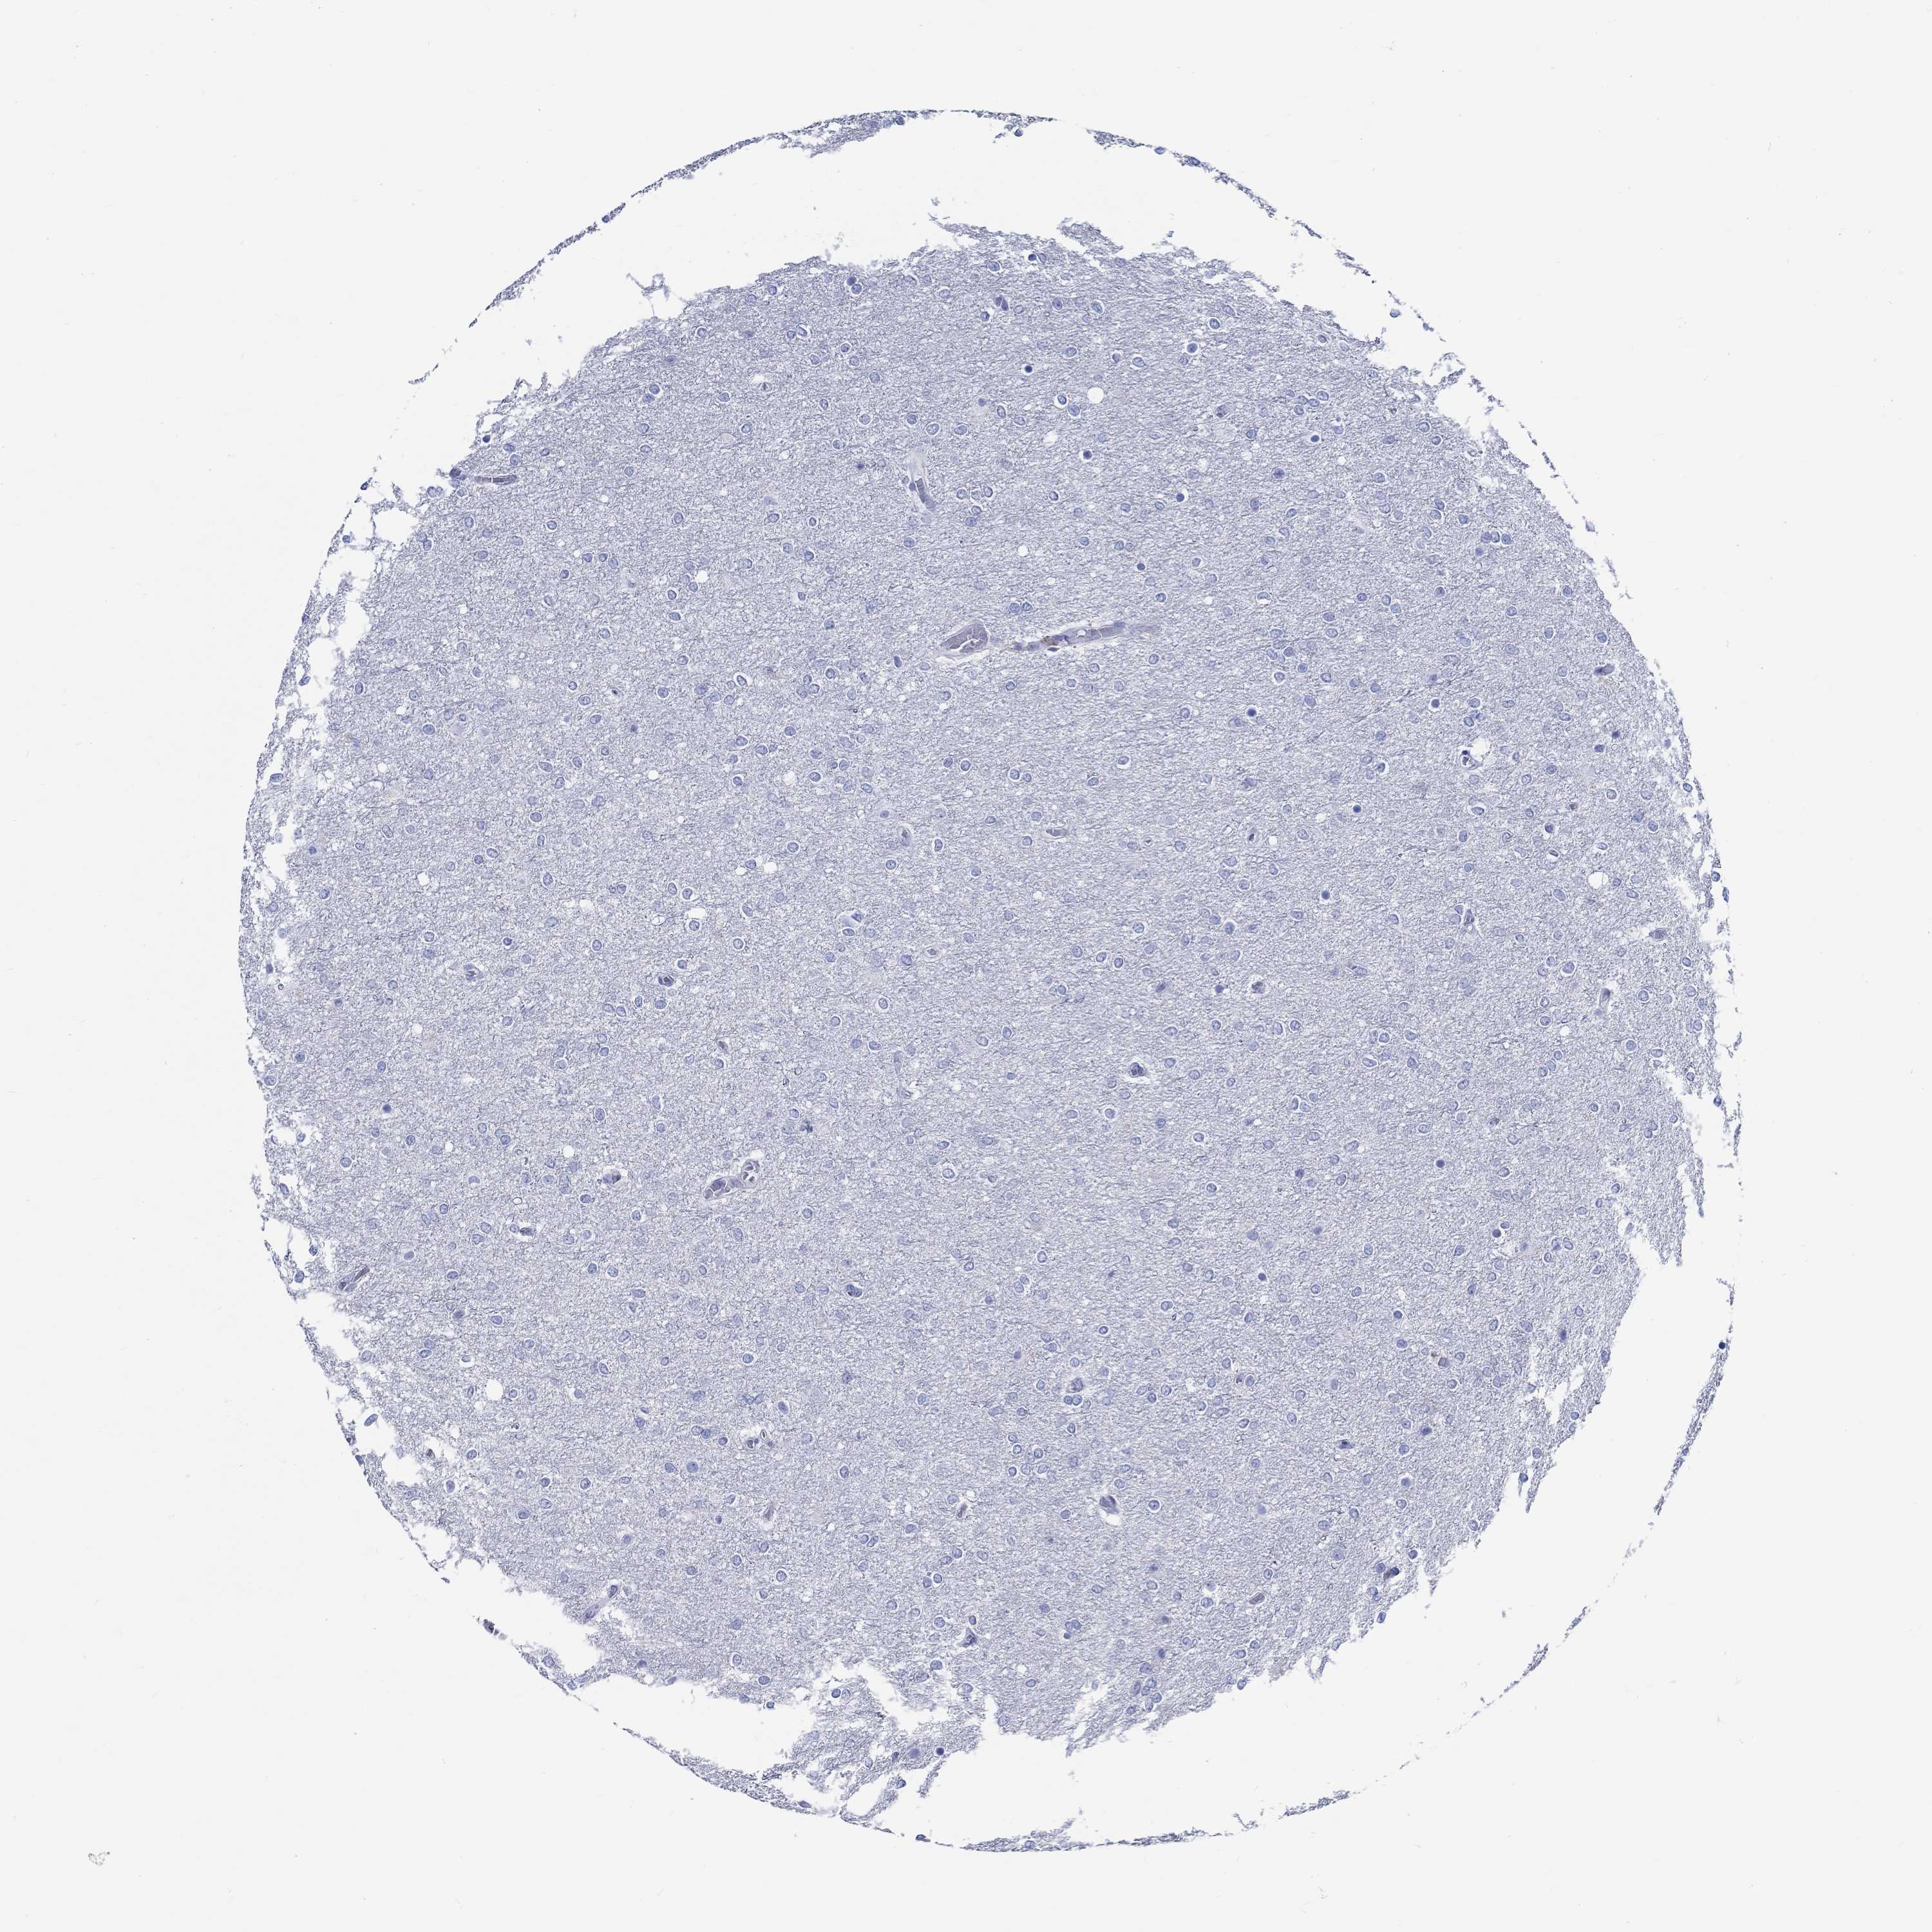

GLIOMA - Protein expressioni

A mouse-over function shows sample information and annotation data. Click on an image to view it in a full screen mode. Samples can be filtered based on level of antibody staining by selecting one or several of the following categories: high, medium, low and not detected. The assay and annotation is described here.

Note that samples used for immunohistochemistry by the Human Protein Atlas do not correspond to samples in the TCGA dataset.

Antibody stainingi

Antibody staining in the annotated cell types in the current human tissue is reported as not detected, low, medium, or high, based on conventional immunohistochemistry profiling in selected tissues. This score is based on the combination of the staining intensity and fraction of stained cells.

Each image is clickable and will lead to virtual microscopy that enables deeper exploration of all samples and also displays staining intensity scores, fraction scores and subcellular localization as well as patient and tissue information for each sample.

Antibody HPA067971

Staining

Glioma, malignant, Low grade

Glioma, malignant, High grade